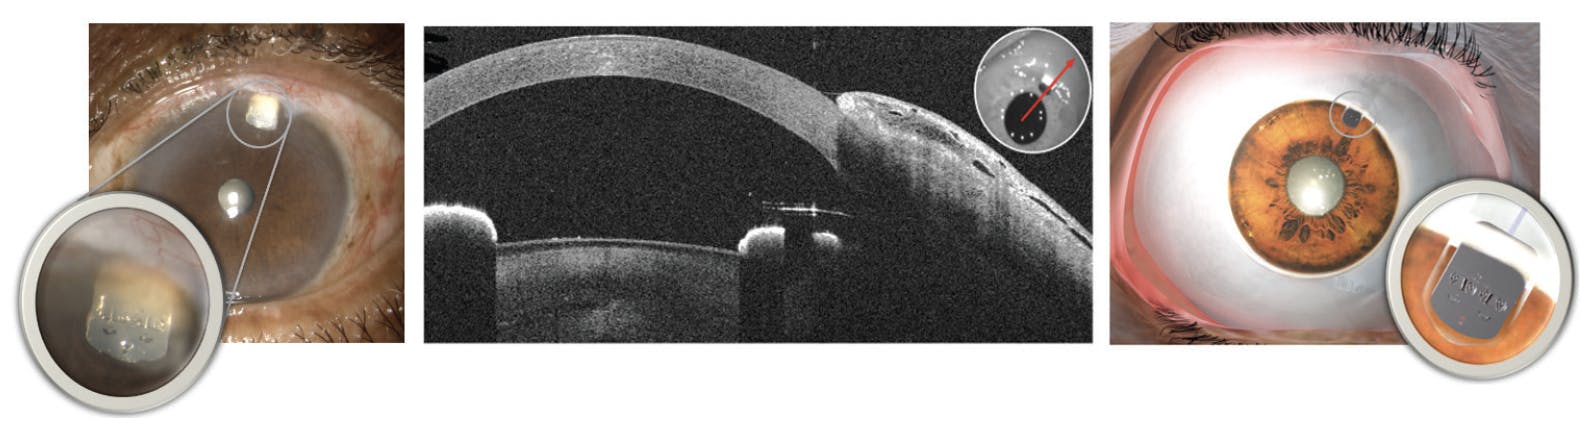

The Calibreye device is composed of nitinol and silicone, both well-established materials with a history of use in intraocular glaucoma implants (Figure 1). The body of the shunt is 1.6 mm wide and 0.3 mm thick and is designed to be implanted through a 1.6-mm keratome incision. The soft, low-durometer silicone, coupled with the low-profile dimension, was selected to conform to the globe and minimize the risk of erosion.

Figure 1. The Calibreye System is a novel titratable aqueous shunt composed of nitinol and silicone. The material, coupled with the low-profile dimension, was selected to conform to the globe and minimize the risk of erosion.

A nitinol valve assembly on the proximal end of the device contains two valves, which control fluid flow through the two outer channels. Each valve is controlled by two actuators, one that opens the valve and one that closes the valve, allowing for reversible, on/off control of aqueous flow. These valve actuators are composed of nitinol with shape memory properties, which can be repeatedly actuated with light energy from a green laser at the slit lamp. An indicator window on the valve assembly provides visual confirmation to the user of the open/closed state.